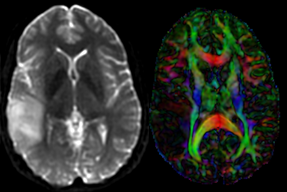

Input

this is the fixed reference image. All images are aligned into this space lleft this is the T2 reference image, serves as target to the DTI baseline, but is itself aligned to the SPGR lleft this is the DTI tensor image, in the same orientation as the DTI Baseline

Registered DTI superimposed on SPGR and T2 registered (cycles show T1 and T2 and color DTI overlay)